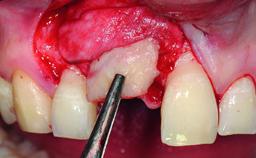

A healthy 28-year-old female patient presented for a consultation on treatment options to restore her upper right central incisor. At the clinical examination, the tooth responded to percussion and palpation. The gingiva was red and slightly swollen, with a mid-facial probing depth of 10 mm. The upper right lateral incisor showed no signs or symptoms, did not respond to exploration and percussion, and the vitality test was positive. The periapical radiograph revealed that tooth 11 had been endodontically treated, with no lesion evident at the apex. A small radiopaque calcified structure surrounded by a narrow radiolucent zone (3 × 3 mm) was present at the apex of tooth 12.

Bone Volume Deficient horizontally, allowing simultaneous augumentation